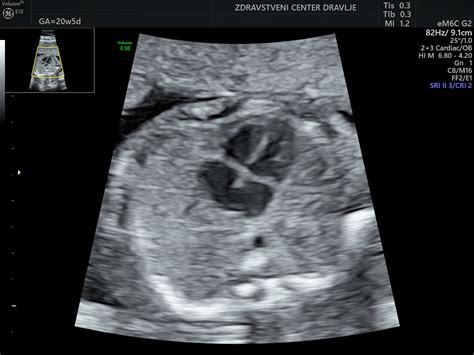

V 21. in 24. tednu nosečnosti ste v drugem trimestru nosečnosti. To je tudi čas za ultrazvočno morfologijo, ki se običajno opravlja med 20. in 22. tednom gestacije. Če se boste odločili za ultrazvok v tem tednu, bo nadvse zanimiv! Ne le, da boste videli otročka na zaslonu, videli boste lahko tudi nekaj čudovitih podrobnosti, kot so možganske poloble in srčni prekati.

Med ultrazvočnim pregledom se preverja gestacijska starost ploda s pomočjo meritev posameznih delov plodovega telesa. Med drugim se merijo prečni presek in obseg glavice, obseg trebuha, dolžina stegnenice ter oceni glavica v treh ravninah. Prav tako se ocenjujejo strukture v zadnji lobanjski kotanji, očnici, obrazni profil, hrbtenica, trebušna prepona, prsni koš, ledvica, sečni mehur ter zgornji in spodnji ud. Med pregledom se ocenjuje tudi posteljica, njena debelina in vstop popkovnice vanjo, ter sama popkovnica.